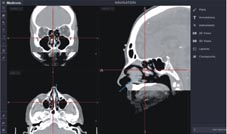

簡單來說,電磁導航的原理是將手術中使用的器械,在機器設置的磁場下準確的追蹤其位置,磁場建立的設置(如:圖四)。在設置完成後,手術中使用的器械位置,均能在導航系統下精確的定位(如:圖五)。這樣的模式讓主刀醫師除了仰賴自身經驗以及內視鏡所見構造判斷手術過程中器械所在的位置,透過導航系統的輔助更能讓主刀醫師對於位置的判讀更有信心。

圖四、導航磁場建立配置